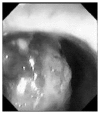

Case report: An 87-year-old man was admitted to our surgical unit with a history of progressive constipation, tenesmus, rectal bleeding and transanal mucous discharge. Preoperative investigations, including CT scan and colonoscopy with biopsy, were suggestive for locally advanced low rectal sarcoma and therefore the patient underwent abdominoperineal resection (APR). However, histopathological examination and immunohistochemistry resulted in a postoperative diagnosis of primary rectal melanoma. The patient died 6 months later due to local and systemic recurrence.